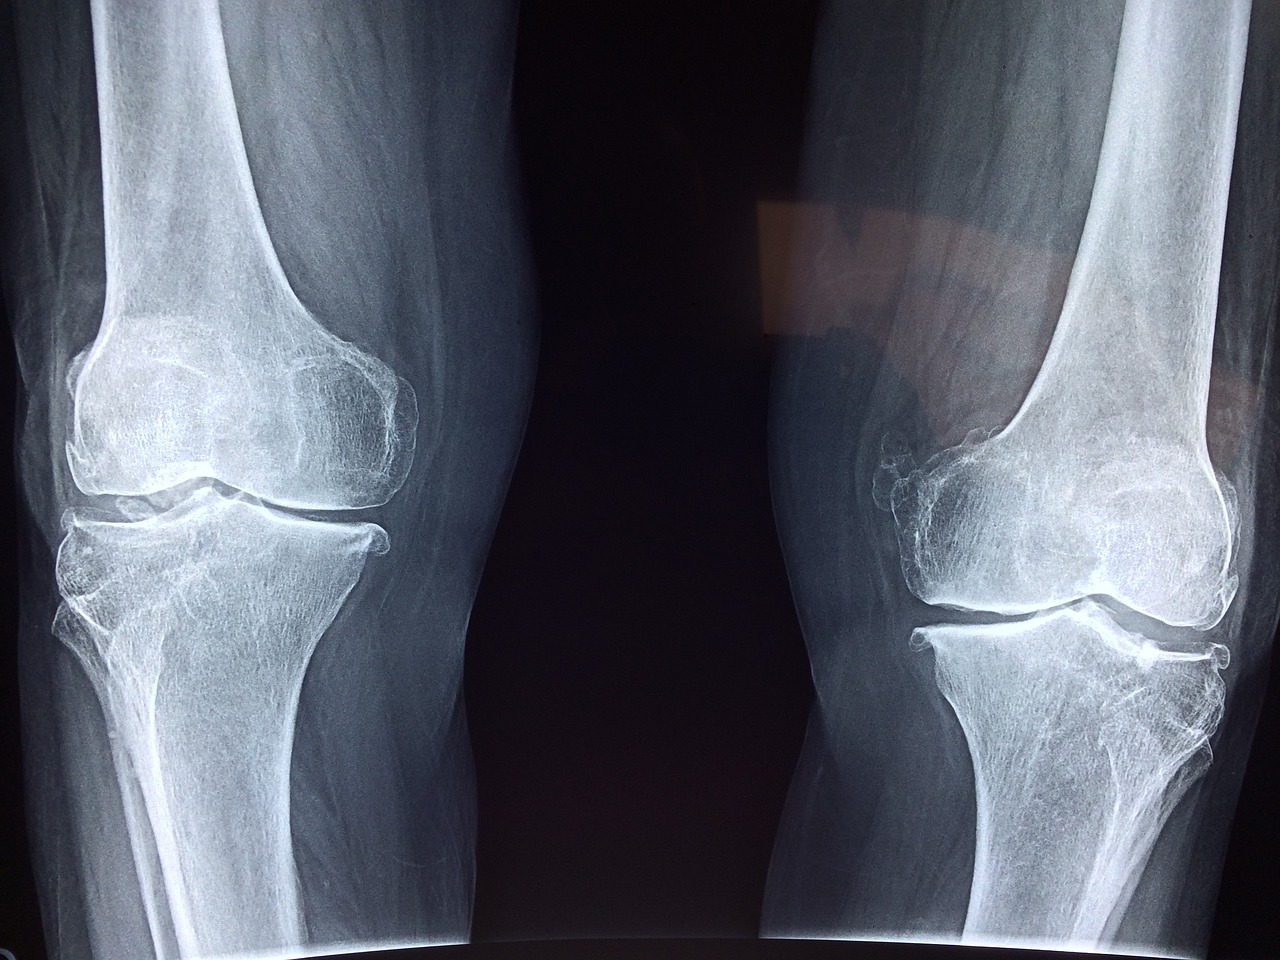

콘드로이친이 부족하면 연골이 뻣뻣해지고 쉽게 손상되어, 퇴행성 관절염으로 이어질 수 있습니다. 꾸준한 관리, 정말 중요하겠죠?!

골관절염 환자를 대상으로 한 연구에서, 콘드로이친 섭취 4개월 만에 통증이 무려 43%나 감소했다는 놀라운 결과가 있습니다.

콘드로이친은 염증 유발 물질을 억제하고, 연골 분해 효소를 막아 통증을 줄여주는 역할을 합니다. 관절 통증으로 고생하시는 분들, 콘드로이친에 주목하세요! (Zhang et al., 2016)

2.5 관절 기능 개선 효과

콘드로이친은 관절의 유연성과 운동 범위를 개선하여, 관절의 뻣뻣함과 부종을 감소시키는 데 도움을 줄 수 있습니다. (Reginster et al., 2001) 활동적인 삶을 원하시는 분들께 희소식이 아닐 수 없겠네요!